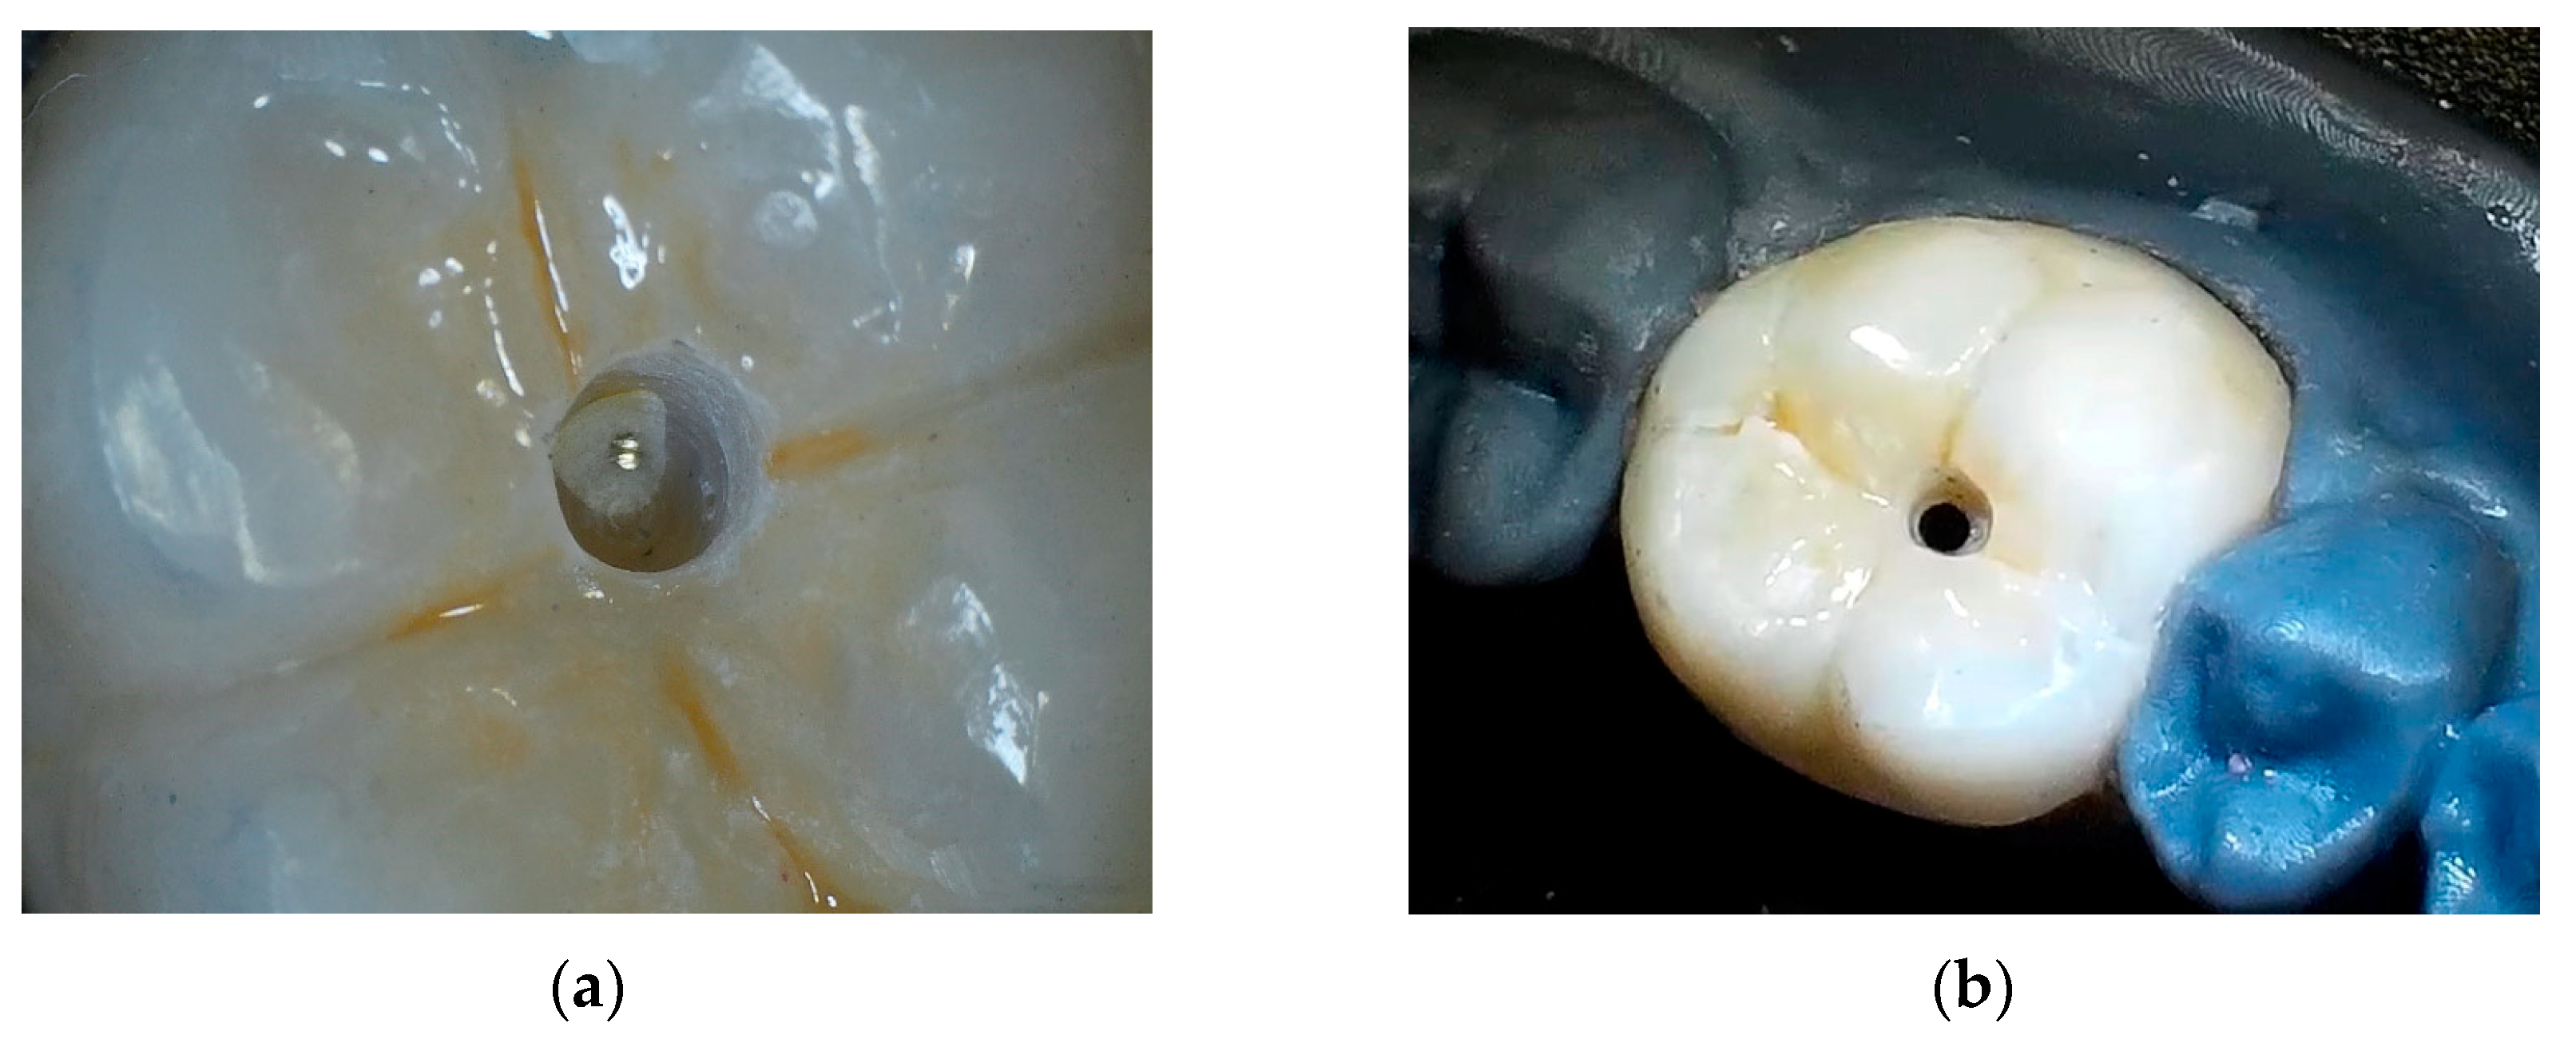

2.5. Procedure